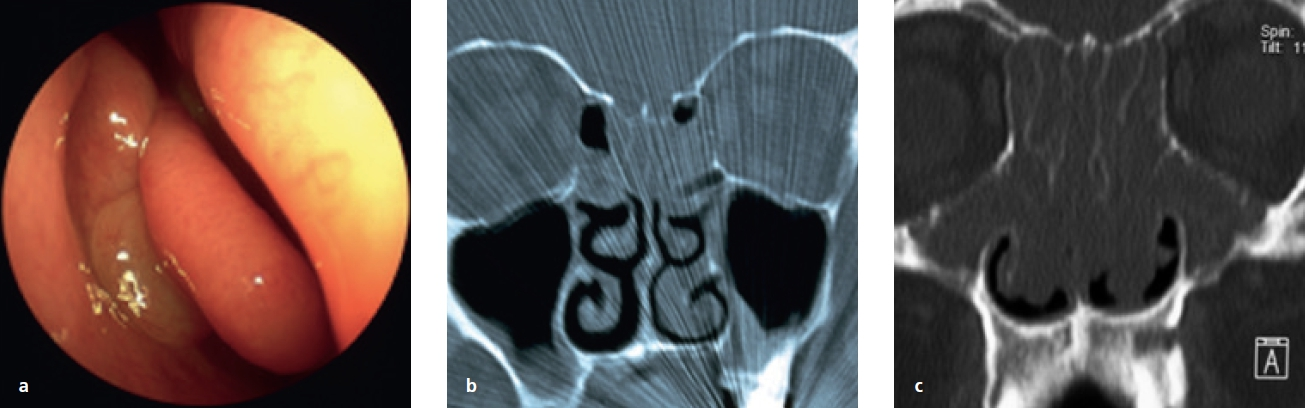

Eine kugelige homogene Verschattung in der Höhle wird im Rahmen der zahnmedizinischen und HNO-Behandlung häufig beobachtet (Abb. 5). Schmerz oder Druckgefühl werden in der Regel nicht angegeben. Bei diesen Retentionszysten handelt es sich oft um Zufallsbefunde, die bei bis zu 14% der Bevölkerung industrialisierter Länder gesehen wurden. Sie sind die Folge umschriebener intraepithelialer Sekretstörungen der Sinusschleimhaut und bedürfen im Falle klinischer Beschwerdefreiheit keiner Behandlung. Nur sehr große Zysten oder homogene Totalverschattungen sollten therapiert werden (Abb. 6). Häufig beklagen die Betroffenen ablaufende Nasensekrete mit unangenehmem Geruch und Geschmack. Im mittleren Nasengang sind endoskopisch eingedickte Sekretbefunde sichtbar (Abb. 7). Besondere Beachtung benötigen inhomogene Verschattungen mit gegebenenfalls sehr dichten Einschlüssen. Hier sind spezifische Infektionen (Pilzball), Tumoren oder Fremdkörper suspekt. Auch im Falle einer deutlichen Restbelüftung muss die Kieferhöhle exploriert und der Befund histologisch geklärt werden (Abb. 8a bis d).

Prof. Dr. O. Kaschke